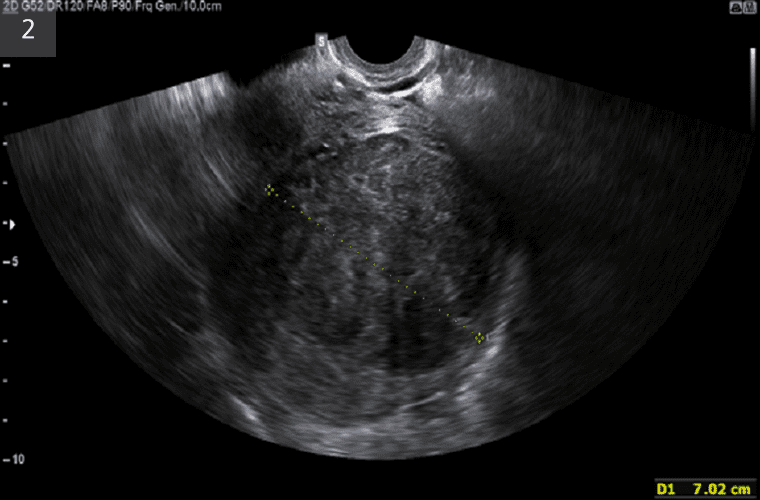

질식초음파로 진단된 자궁근종

질식초음파로 진단된 자궁선종